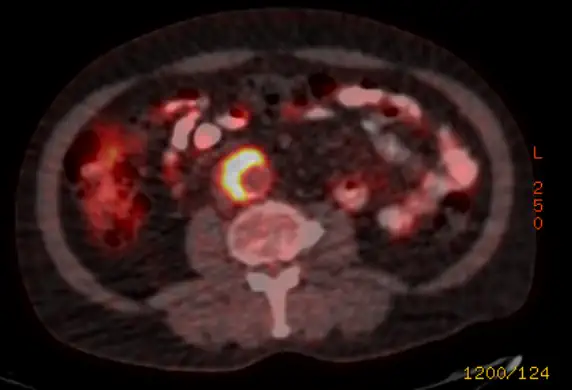

- Assess blood flow. Abnormal blood flow to the foot will suggest the spots are gangrene. Remember to think beyond peripheral artery disease in the context of evaluating black spots on toes. For example, reduced blood flow can result from a thrombus or an artery dissection.

- Look for a source. The most common places to look are the heart and the aorta. So, getting an echocardiogram (“heart ultrasound”) and CT scan of the aorta makes sense.

- Does the patient have another condition that could explain the spots on the toes? If they do, that can be alarming. For example, if a patient has atrial fibrillation, the spots on the toes could have come from the heart. Similarly, a patient with a known infected heart valve could throw a piece of infected material to the toes. Clot from an abdominal aortic aneurysm (AAA) might reach the toes. That phenomenon has the sad name of “trash foot”.